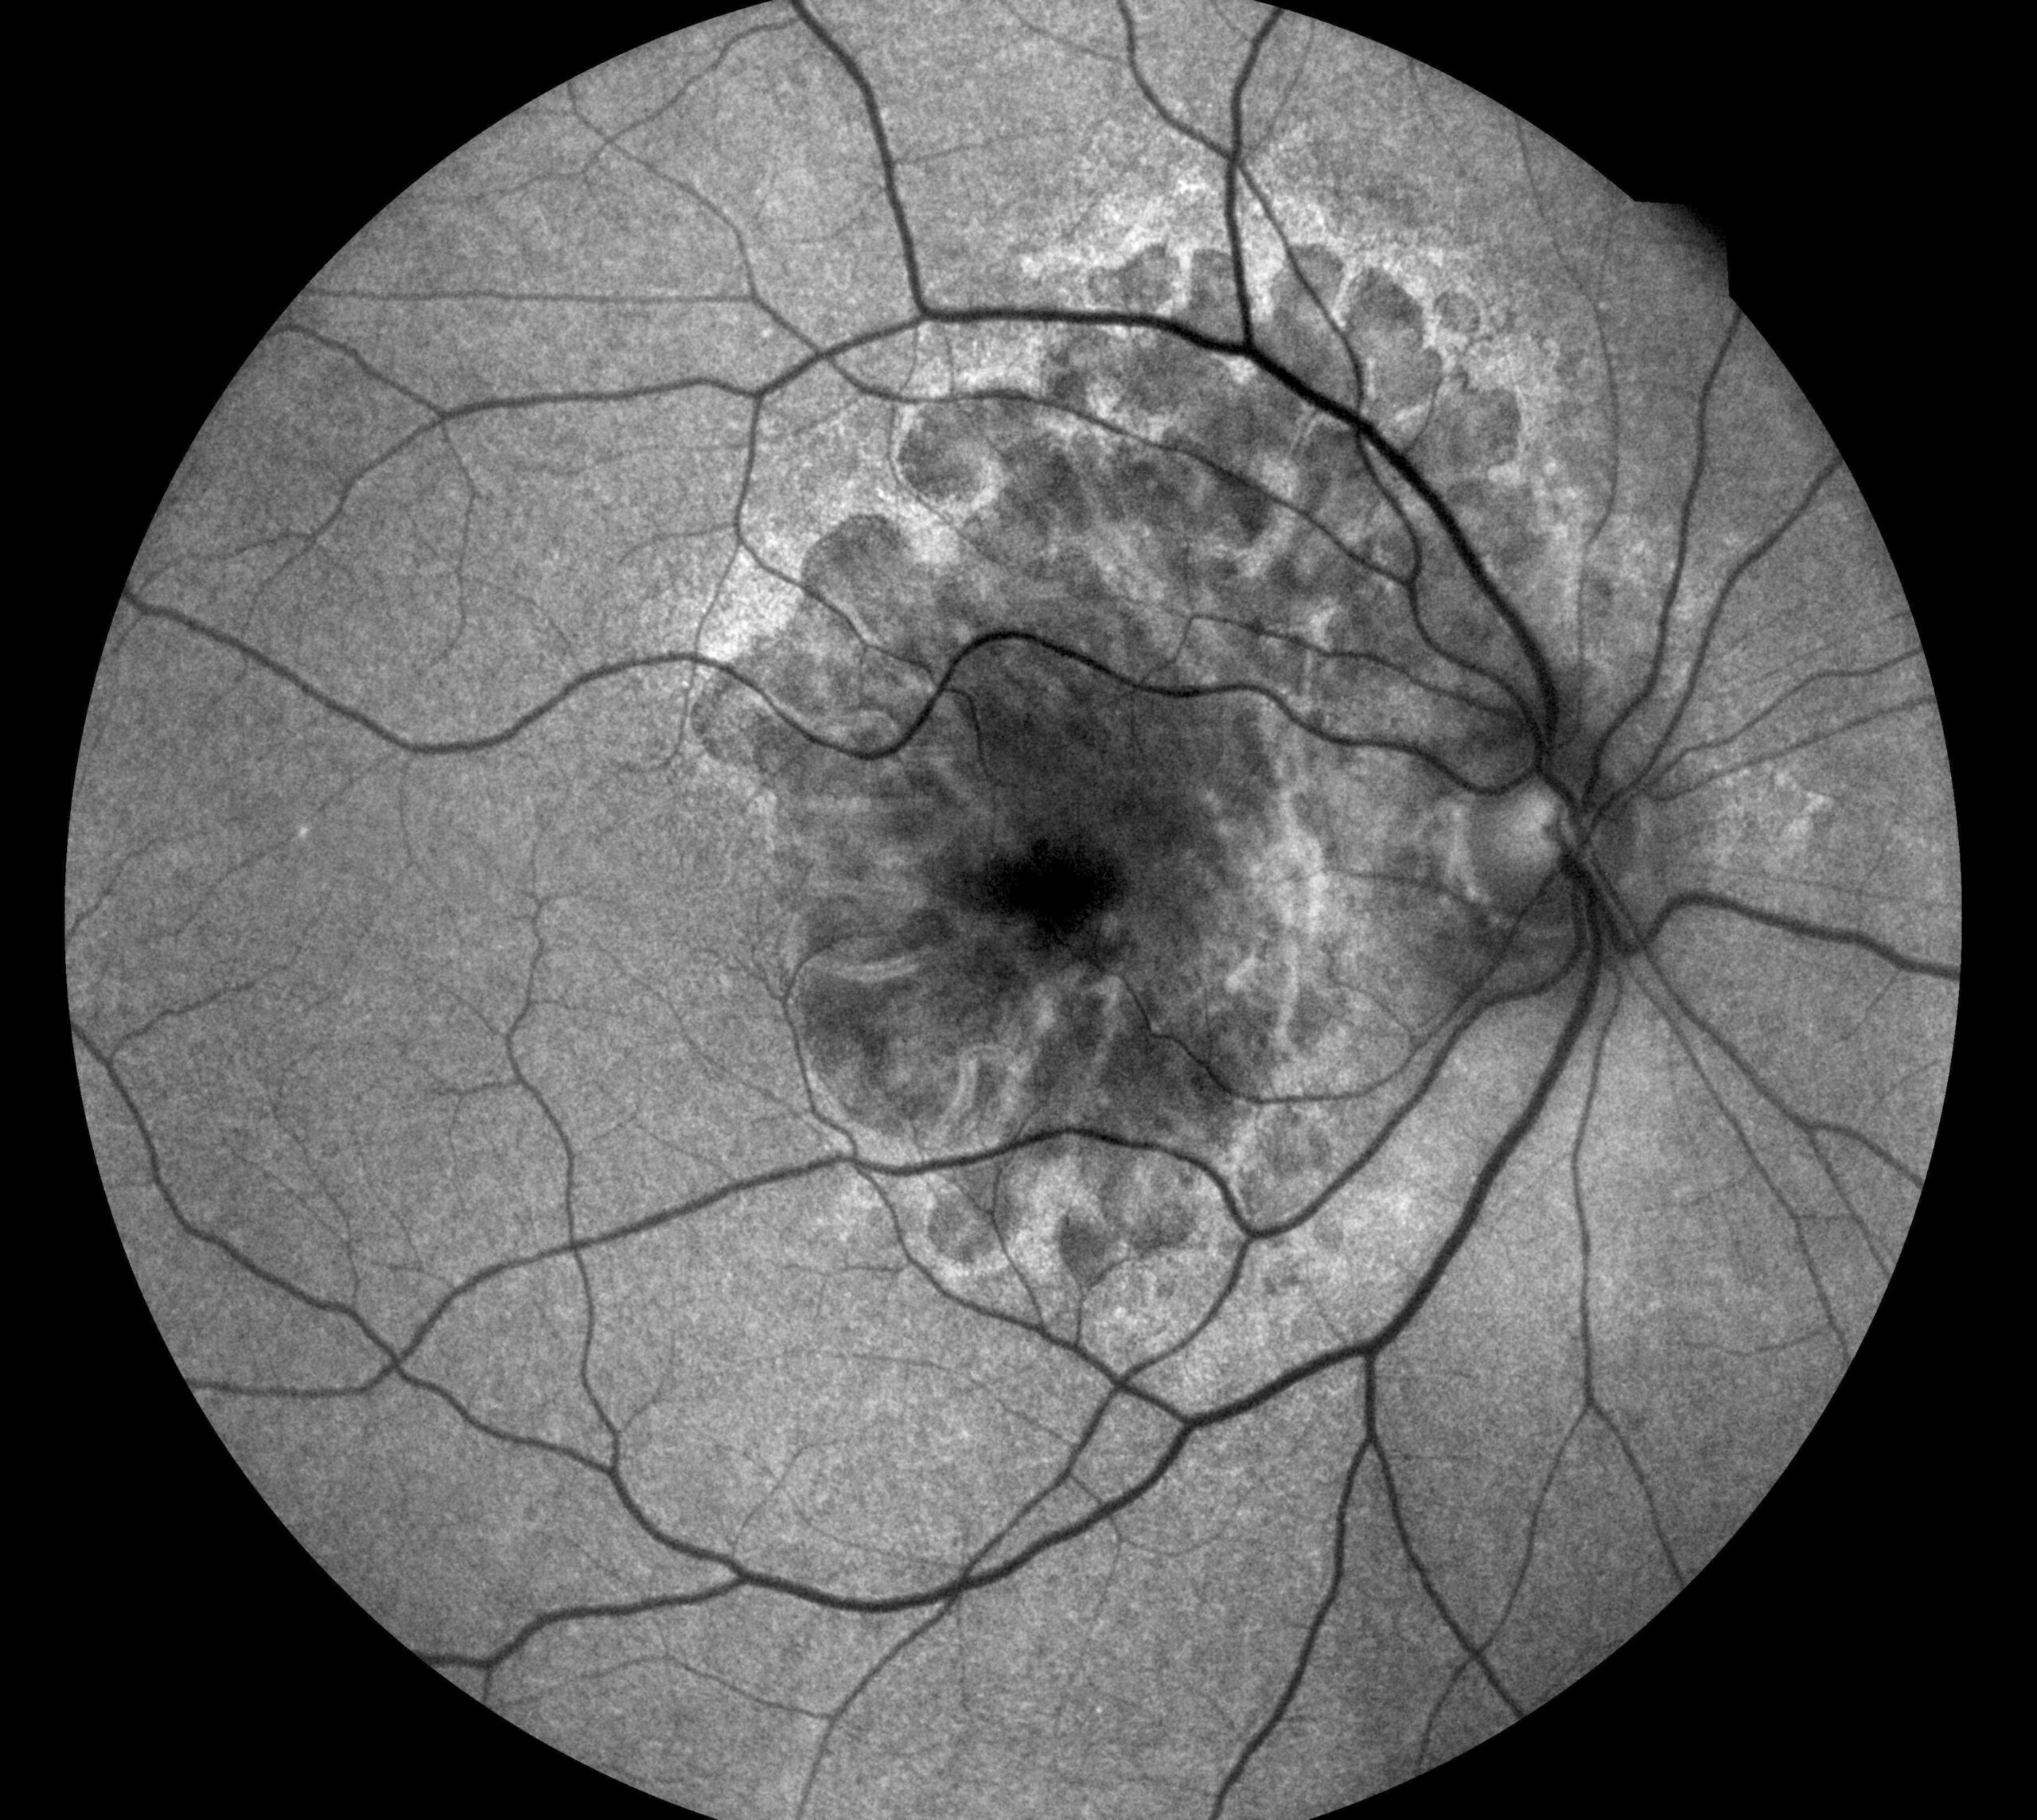

✓ Autofluorescence mode